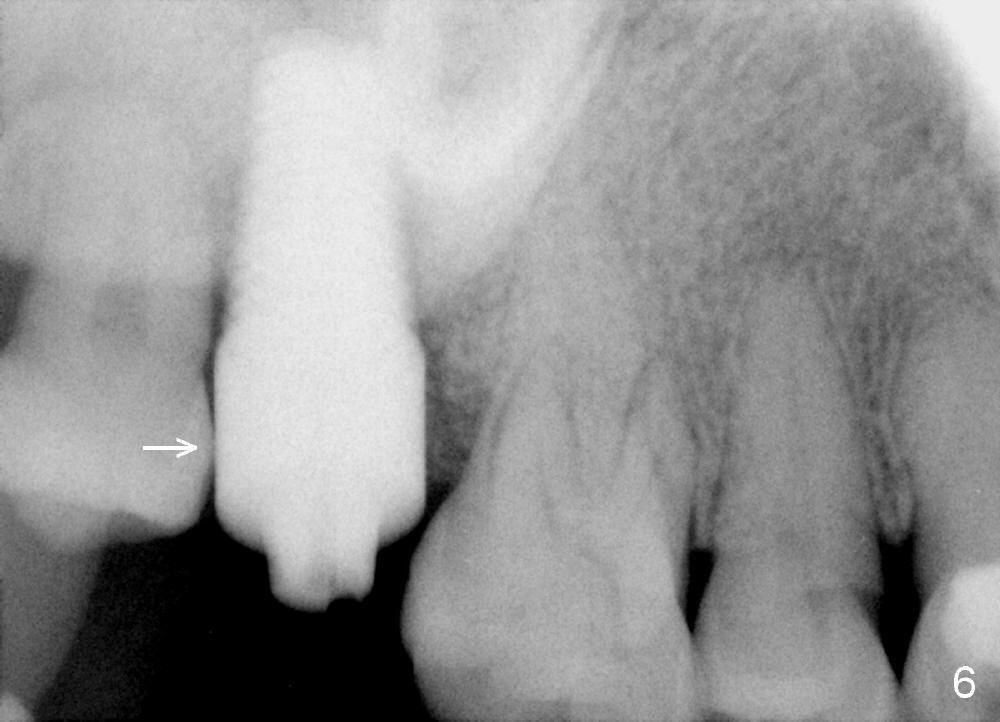

A 48-year-old lady is a dental phobic and has generalized chronic periodontitis. Bone loss around the tooth #2 has been severe for the last 5 years (Fig.1,2 *). Finally she agrees to have #2 (symptomatic) extracted and immediate implant placed (Fig.3 I). A 7x17 mm implant has to be used to achieve primary stability. The remaining buccal and lingual gaps are filled with allograft and membrane (Fig.4 *). Fig.5 shows that there is a space between the tooth #1 (asymptomatic) and the immediate implant (I). The wound/socket is protected by applying perio dressing around an abutment (Fig.6 A). Postop the patient is pain free; the perio dressing dislodges by itself. She returns 3.5 months later for restoration; but the tooth #1 has shifted mesially (Fig.6 arrow). The patient is not so willing to have #1 removed. Bands and bracket are placed in the neighboring teeth including a provisional crown to move the shifted tooth (with mobility) distally (Fig.7,9). The 2nd reason for #1 shifting is abnormal occlsual scheme on the right posterior region (Fig.8); mobility of #1 is the 1st one. The 3rd one is probably bruxism. In 5-6 weeks, the tooth #1 has moved to a desirable position (Fig.10, as compared to Fig.3,5). There is enough space for restoration (Fig.11,12).